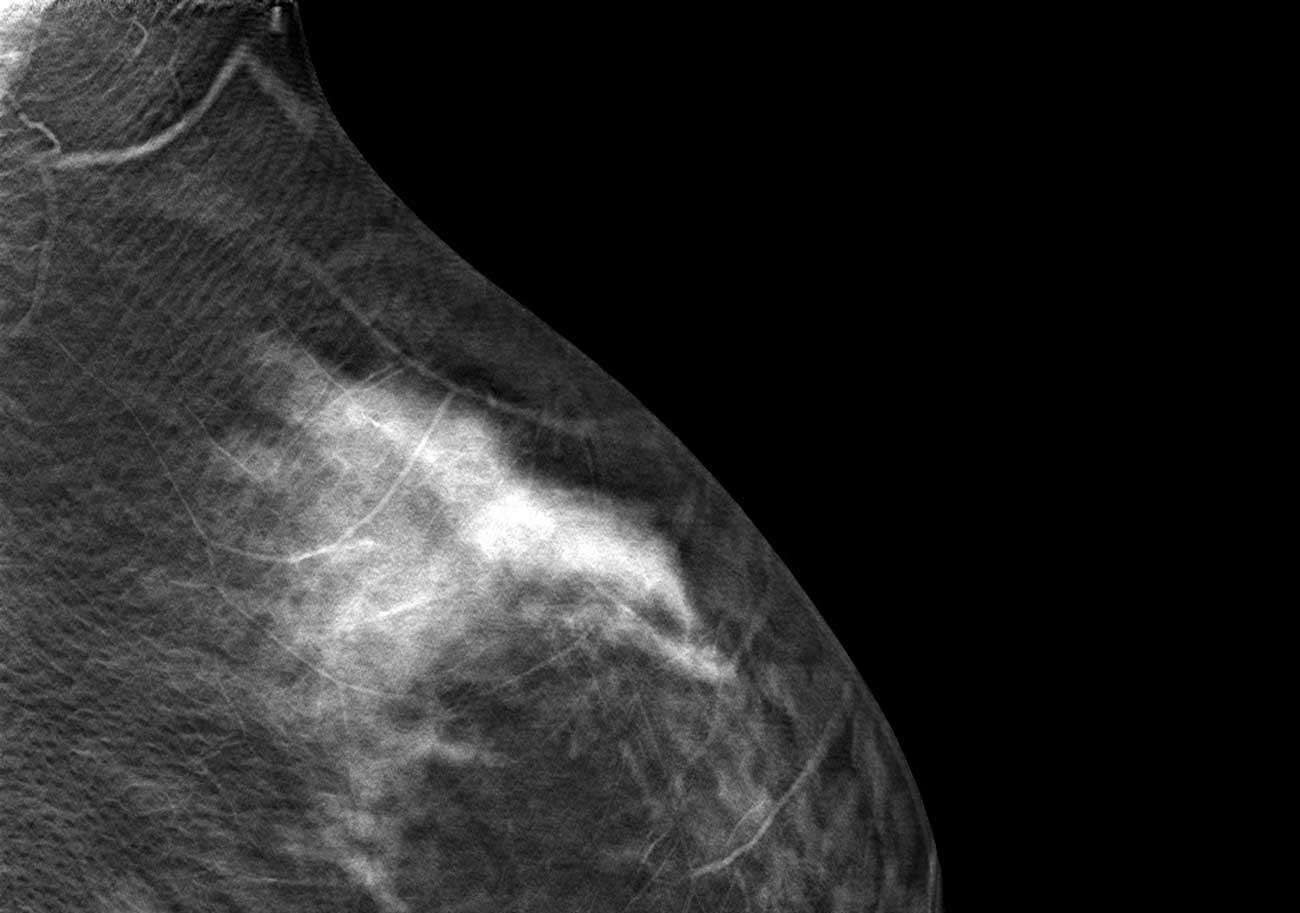

Best views of the ‘questionable distortion’ mentioned on report

- Architectural Distortion L MLO Breast Tomosynthesis

- Architectural Distortion L CC Breast Tomosynthesis

Ok doesnt help or answer ur question. I just have to say though white in the scan (referencing featured image), it looks like a hummingbird. – Melissa